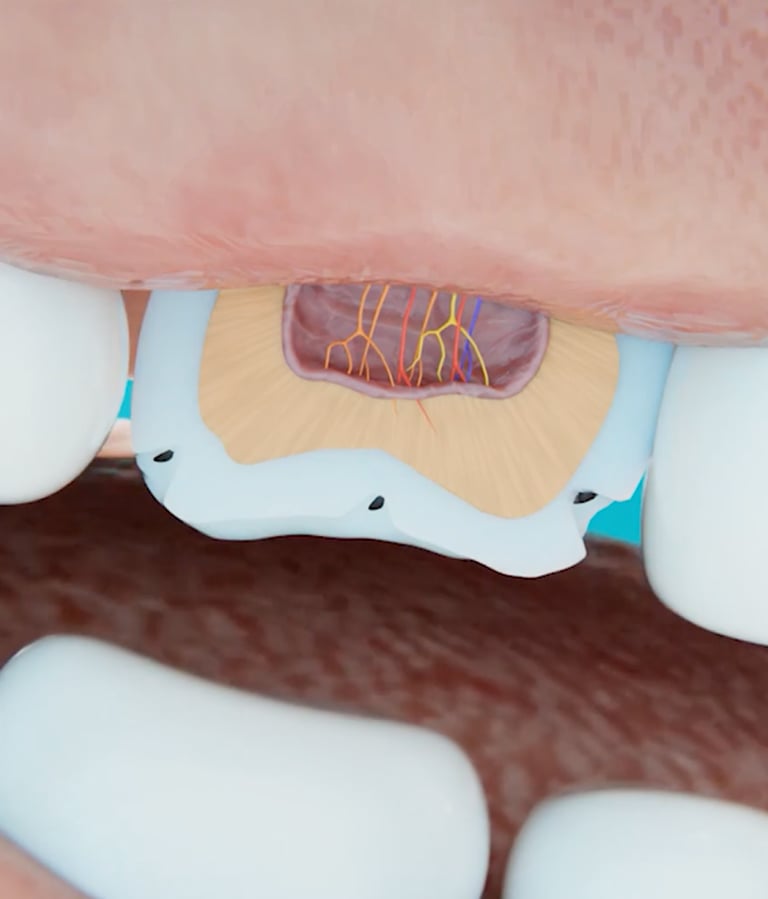

Every piece of Larineco™ is infused with microscopic particles of Nano Hydroxyapatite — the very same mineral that makes up 97% of your tooth enamel. As you chew, these particles bond with your enamel, filling in tiny cracks, smoothing rough surfaces, and reinforcing weak spots to make your teeth stronger and more resilient over time.